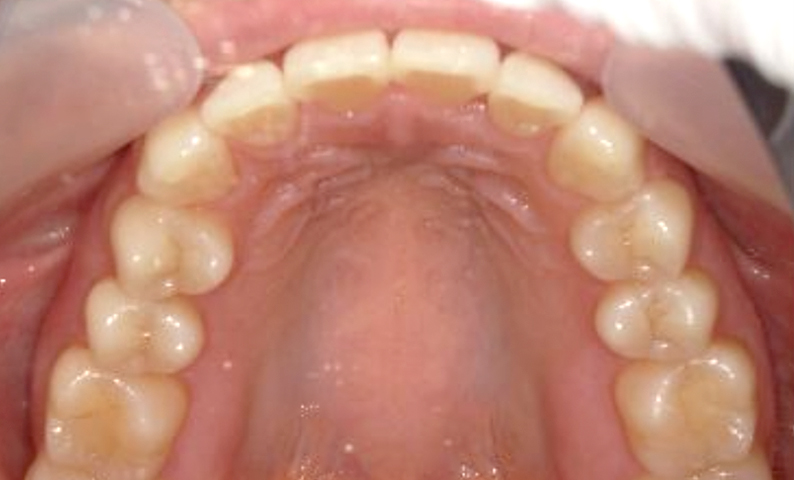

症例_006 前歯「捻転歯」症例

治療期間:7ヶ月金額:30万円+税20代女性少しのねじれ歯の形態修正上の前歯だけ

| Before | After |